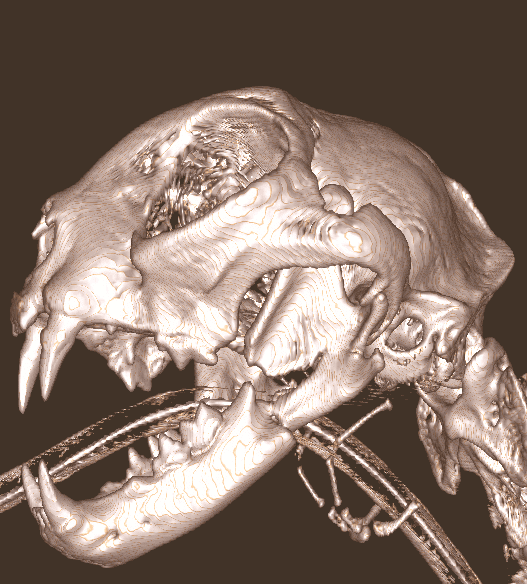

Cone Beam Computed Tomography

The Center now provides advanced imaging via cone beam CT. Cone beam CT is excellent for visualization of bony structures of the skull, nasal cavity, teeth, and ears. Cone beam CT is especially helpful for diagnosing dental disease and evaluation of jaw fractures. It can also be useful for evaluating the sinuses and tympanic bulla. Cone beam CT can be used in conjunction with nasal biopsy and culture to evaluate nasal discharge whether chronic or acute.

Repair of Maxillofacial Fracture

Pets can be involved in trauma that can cause fractures to their head, teeth, and jaw bones. Correctly repairing these fractures is extremely important for your pet to have normal function of their mouth. If a jaw fracture is allowed to heal in an abnormal position, your pet may have great difficulty chewing and can be in significant pain. Many fractures can be successfully treated with minimally invasive oral procedures, but more complicated cases may require bone plating techniques. The Center offers cone beam CT imaging which provides extremely detailed images of the bones of the head and skull. Advanced imaging with CBCT facilitates selection of the best surgical technique to get your pet back to eating and comfort as soon as possible.